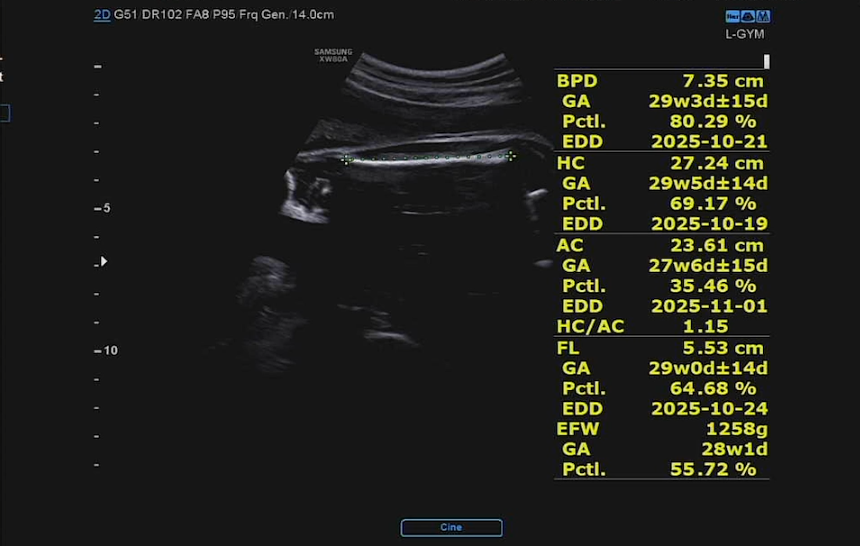

1. BPD (Biparietal Diameter, 대횡경)

- 7.35 cm

- GA (Gestational Age): 29주 3일 ± 15일

- 백분위수 (Pctl): 80.29% → 평균보다 큰 편

- EDD (Estimated Due Date): 2025-10-21

- 의미: 태아 머리의 좌우 폭을 측정한 값으로, 정상 범위이며 발달이 비교적 큰 편입니다.

2. HC (Head Circumference, 머리둘레)

- 27.24 cm

- GA: 29주 5일 ± 14일

- Pctl: 69.17% → 평균보다 조금 큼

- EDD: 2025-10-19

- 의미: 머리둘레도 정상 범위, 평균보다 약간 큼.

3. AC (Abdominal Circumference, 복부둘레)

- 23.61 cm

- GA: 27주 6일 ± 15일

- Pctl: 35.46% → 평균보다 작음

- EDD: 2025-11-01

- 의미: 복부 성장 속도가 머리에 비해 조금 뒤처진 편. 영양상태나 성장 속도에 따라 변화할 수 있음.

4. HC/AC 비율

- 1.15

- 의미: 머리둘레 대비 복부둘레의 비율로, 지금은 머리가 약간 더 발달한 상태.

5. FL (Femur Length, 대퇴골 길이)

- 5.53 cm

- GA: 29주 0일 ± 14일

- Pctl: 64.68% → 평균보다 약간 큼

- EDD: 2025-10-24

- 의미: 다리 길이도 정상 범위.

6. EFW (Estimated Fetal Weight, 추정 태아 체중)

- 1,258 g

- GA: 28주 1일

- Pctl: 55.72% → 체중은 평균 범위.

태아 주제에 팔뚝이 남자답다. 1.258kg 드디어 kg 단위를 쓰게 되는구나. 체중이 다 머리로 갔는지 복부둘레에 비해 머리둘레가 비교적 크단다. 그래도 엄마 아빠 둘 다 대두(?)가 없으니 이 또한 별로 걱정되는 부분은 아니다.